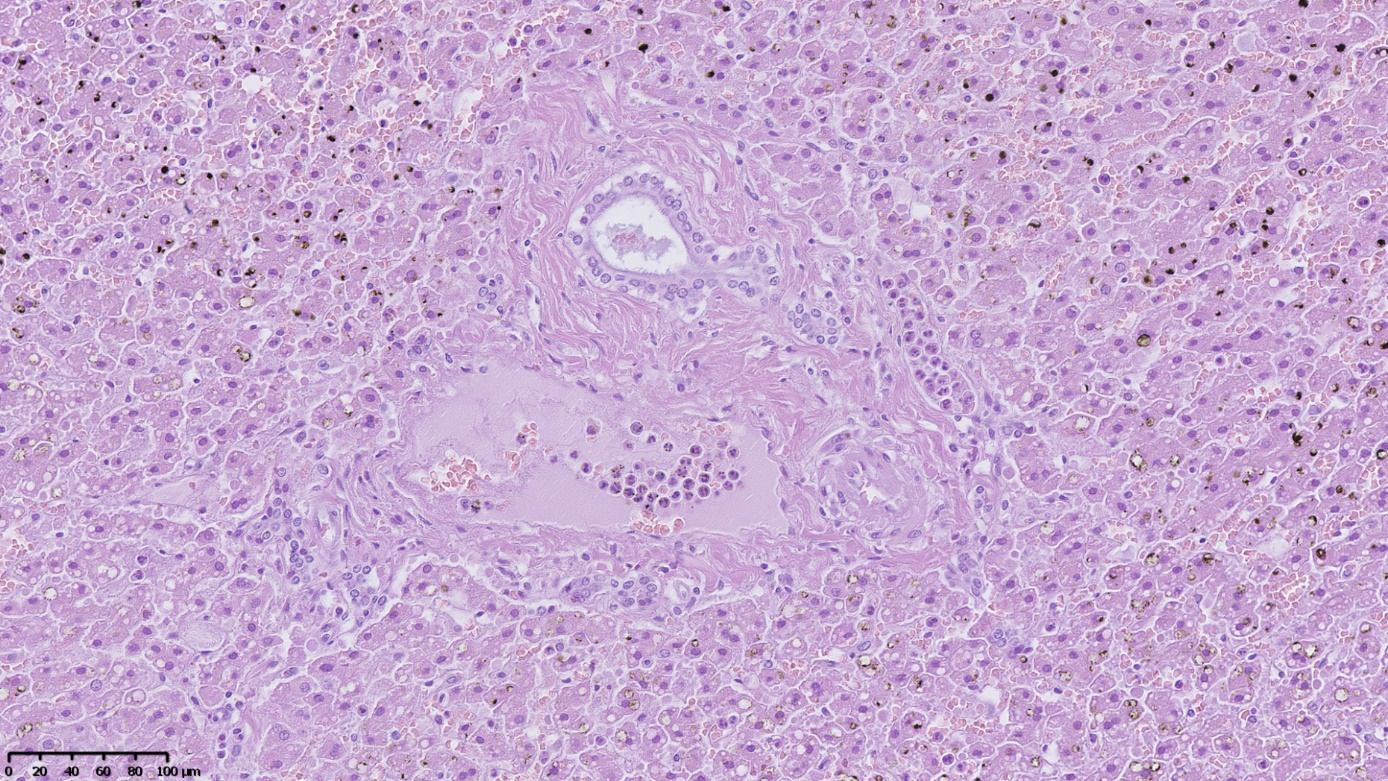

Morphological changes in the liver typically represent focal hepatocyte degeneration. Only in one case did they demonstrate signs of active inflammation and developing fibrosis (Figure 3). The nature of the observed changes does not allow for a clear connection with the use of “legal highs”, as the same changes may be associated with metabolic disorders, obesity, alcohol abuse, or viral hepatitis.

Figure 3. Numerous neutrophils are visible in the lumen of the venous vessel of the biliary space and in the dilated sinusoidal vessel. There is evidence of mild fibrosis of the biliary space and microvesicular steatosis of the hepatocytes. Numerous yellowish-brown artifacts associated with autolysis are visible in the upper and lower portions of the image. Hematoxilin & eosin stain, magnification ×200.